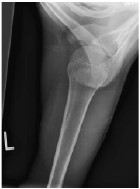

(3)X 线片可明确移位情况,同时摄双侧肩锁关节 Zanca 位片(球管射线向上成角10°-15°前后位)对比,可发现患侧肩锁外端与肩峰间距离较健侧增大;有半脱位和全脱位之分(锁骨外侧端与肩端完全分离)。必要时拍应力位片,即患者两手分别提重物约 2.5 公斤物件后拍肩锁关节正位片。

图1

图 1 . Zanca 位片 AC肩锁关节Zanca 位片是在上肢负重与不负重情况下,投射角度与肩锁关节呈10~15º夹角,有助于发现肩锁关节部位小的骨折或者脱位。